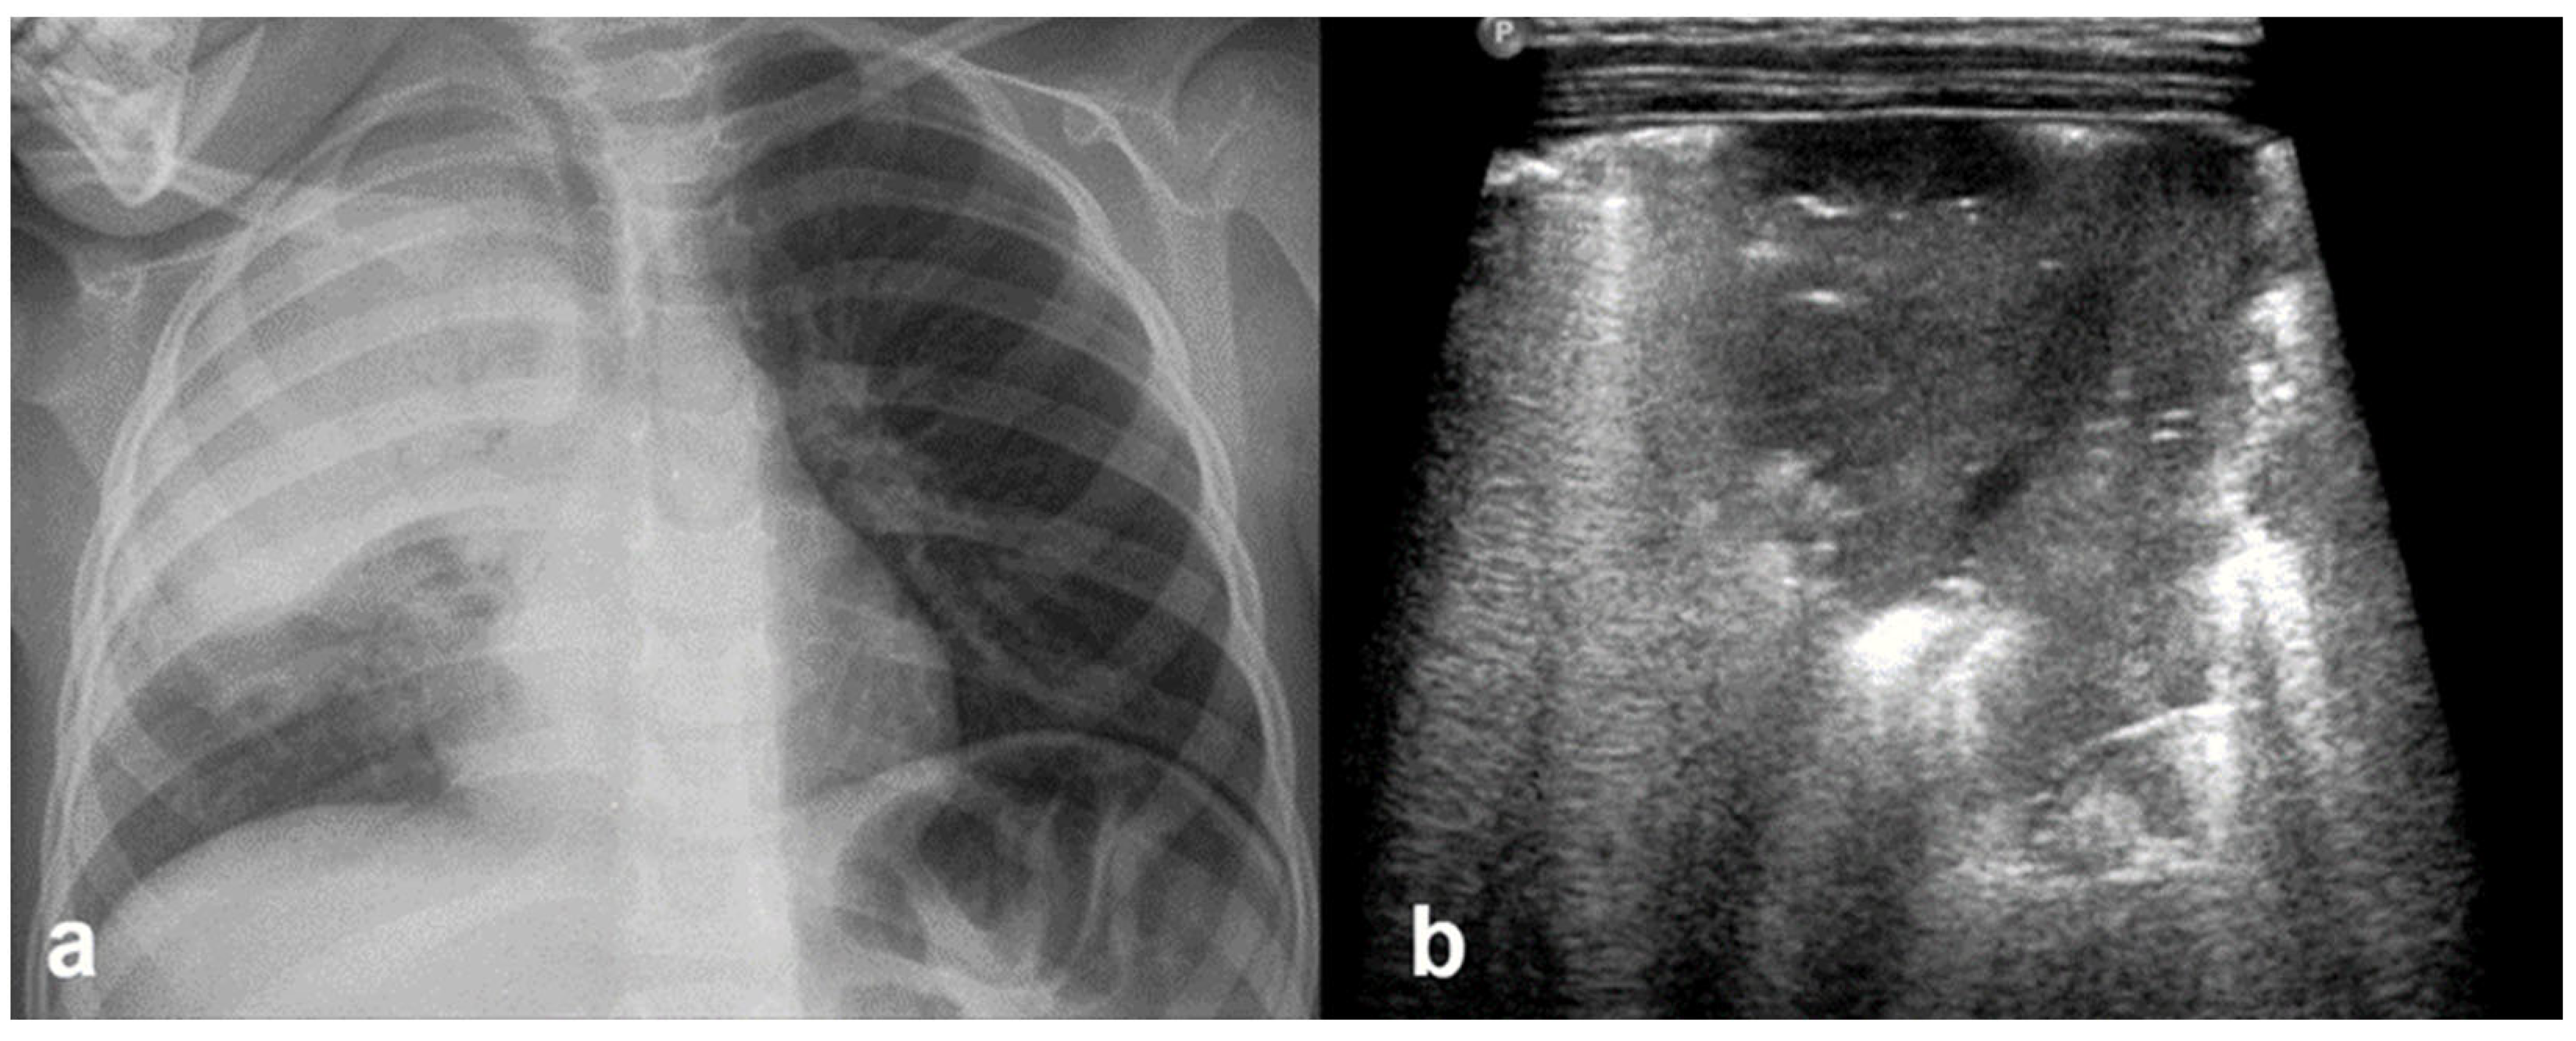

Normal to mild RDS: by chest X-ray (a); by LUS (b).

Figure 14.

Severe RDS shown on chest X-ray (a); LUS (b). The ability of the LUS to characterize the severity of the RDS is debatable.